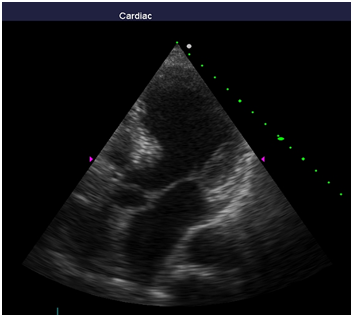

Repeated echocardiography revealed the zone of violation of local contractility (akinesis and pronounced hypokinesis) all segments on the medial and apical level with the formation of acute left ventricular aneurysm, a marked reduction of EF (23%), hyperkinesis all segments at the basal level (Figure 4-8). Troponin test was strongly positive (Figure 9). The patient is re-examined by a cardiologist, on the basis of ECG, Echo pattern, and the presence of markers of myocardial damage diagnosed with acute myocardial infarction in type 2 complicated by development of acute left ventricular aneurysm, acute heart failure Killip class IV. We carried out differential diagnosis between stress cardiomyopathy and myocarditis.

Figure 4 Echocardiography: PLAX, hyperkinesis of the basal segments with apical ballooning.